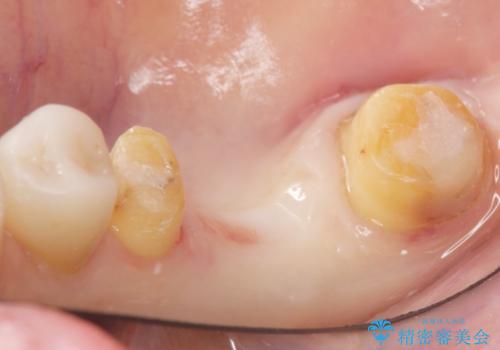

- 奥歯の違和感を主訴に来院された患者様です。

右下の銀歯(右下6)を除去したところ、虫歯が深く保存不可能な状態でした。